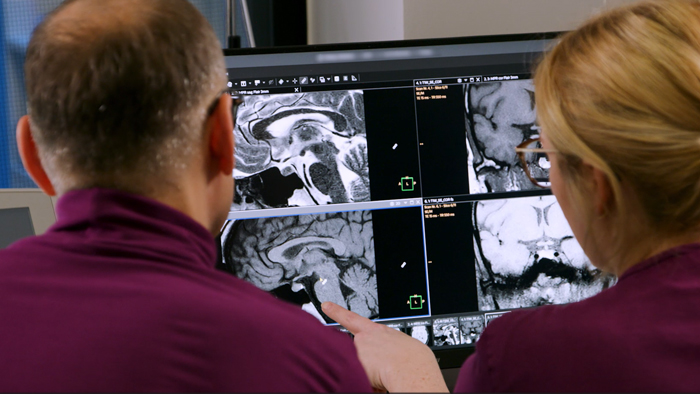

Then, because the computing capacity is so large, we have the images immediately available on the large screen. Higher resolution is very valuable. From the high-resolution 3D sequences, excellent multiplanar reconstruction can be obtained. This makes it easier and faster for us to diagnose and create reports. And while the patient is still lying in the magnet, we can already view the images and make a diagnosis. When the patient comes out, I can immediately ask whether what I see corresponds to the symptoms.”

“The big 27-inch 4K high resolution screen makes a total difference. It shows the large planning images with much higher resolution than we were used to. Anatomic landmarks can be more easily identified, which advances the process. Now it is much easier and faster to plan the new sequences and it’s easier for us to find lesions,” says Dr. Schröter.

Powerful GPU rapidly provides images and reconstruction on large screen

Another important part of MR Workspace is the graphics processing unit (GPU), which allows on-the-fly reconstruction times for images acquired with SmartSpeed. “In addition to seeing razor-sharp images on the large 4K monitor, we also have better and faster reconstruction of the images. Using this extremely high resolution, we sometimes have sequences with up to 800 individual images. The GPU then manages to convert them in a matter of seconds into multiplanar reconstructions. Very impressive.”